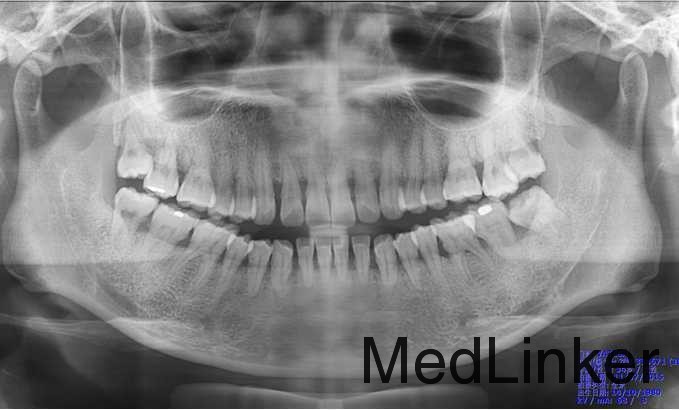

曲断示:全口牙槽骨水平吸收根长1/2,36近中牙槽骨角形吸收。18,28,38,48阻生。

诊断:侵袭性牙周炎

这个应该属于广泛性侵袭性牙周炎,全口普遍性的牙槽骨吸收,但是好像没有明显的垂直性骨吸收,基本上都是水平性骨吸收。